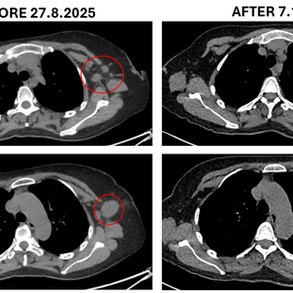

ECCT as sole Alternative Treatment for Testicular Cancer Metastasis to Lungs and Lymph Nodes